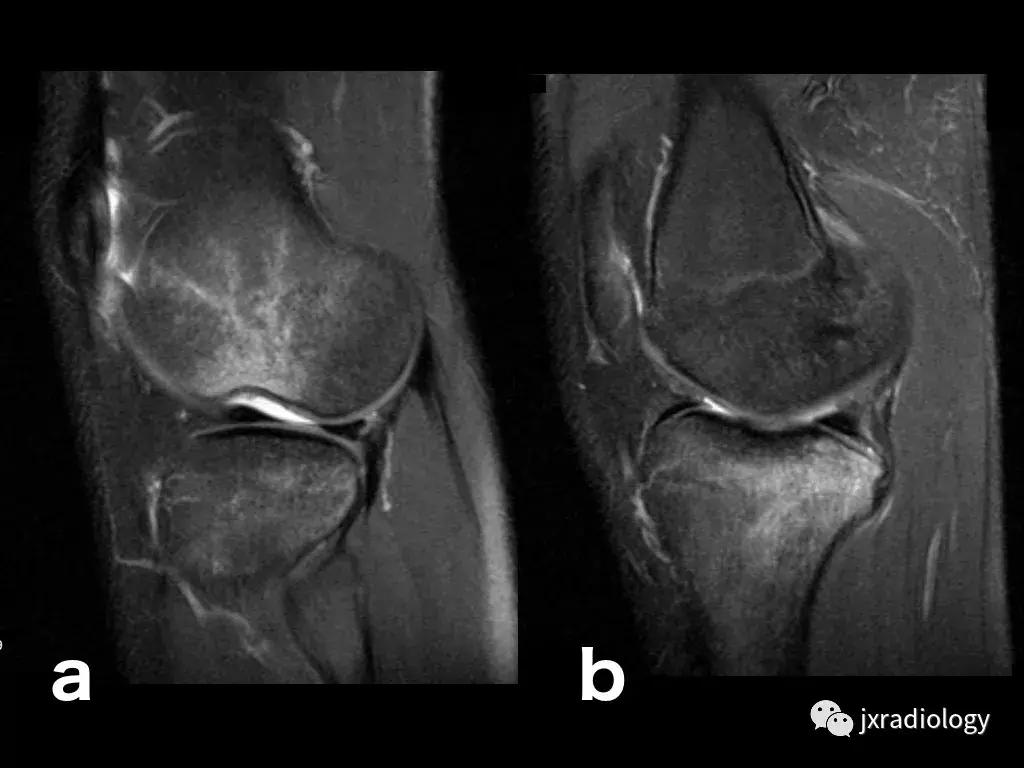

图20:患有血红蛋白病的患者(例如镰状细胞性贫血),在这种情况下,容易发生继发于毛细血管阻塞的骨坏死。 这种阻塞导致毛细血管静水压升高,造成水敏性序列中低信号骨梗死周围的高信号水肿。 这是充血性骨髓水肿的一个例子(由于骨髓空间毛细血管床液体流出受损)。 该患者还表现出广泛的红骨髓转化,如T1-WI中的骨髓信号所示(远低于周围脂肪组织并略高于肌肉组织)和DP-FS-WI(未完全饱和,保持略高信号)( a:冠状面DP-FS-WI; b:冠状面T1-WI; c:轴向T1-WI; d:矢状面DP-FS-WI)。